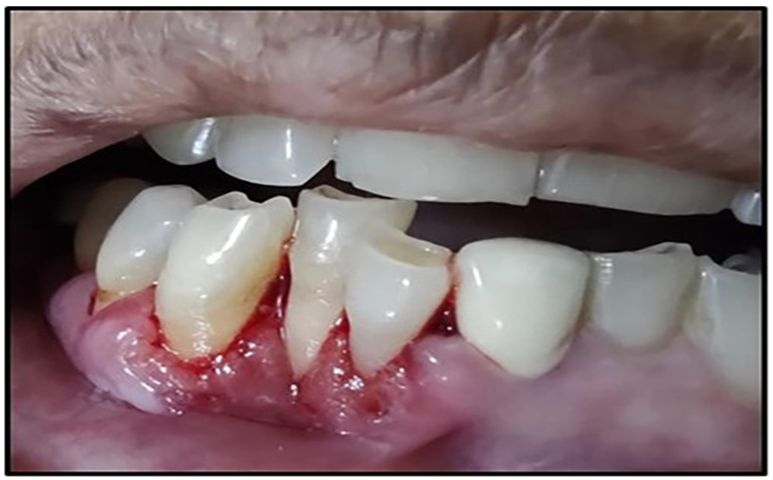

Gum Recession

As the disease gets worse, the gums pull away from the teeth, exposing the tooth roots, which can make teeth more sensitive (Lindhe et al., 2015).

Pus Discharge (Suppuration)

Sometimes, pus may come out of these pockets, showing an active infection and tissue breakdown (Socransky & Haffajee, 1991)